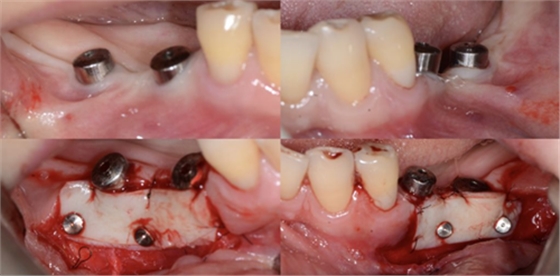

比如strip技術,如下圖:

上圖中,種植體唇側缺乏附著齦,從上腭取瓣,常規(guī)做法:取長而寬的齦瓣,這樣供區(qū)面積大,術后疼痛重。

為了減少痛感,從雙側上腭取多條長而窄的齦瓣進行移植,這樣每個供區(qū)的傷口都比較窄,可以減少術后的痛感。